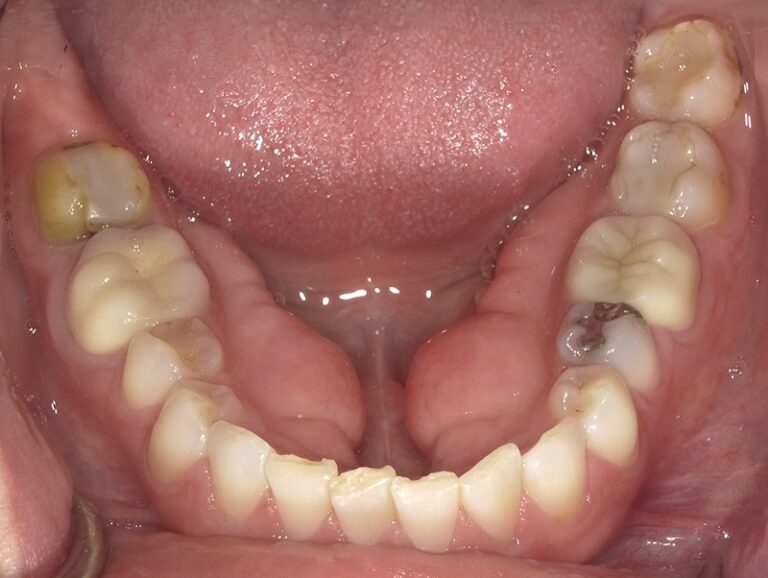

We began this patient's cosmetic journey with SureSmile clear aligners. We were able to accommodate patient's request of a shorter aligner treatment length, and move on to porcelain restorations. We placed 12 upper crowns and 6 lower veneers, thus giving her a beautiful new smile in a shorter timeframe!